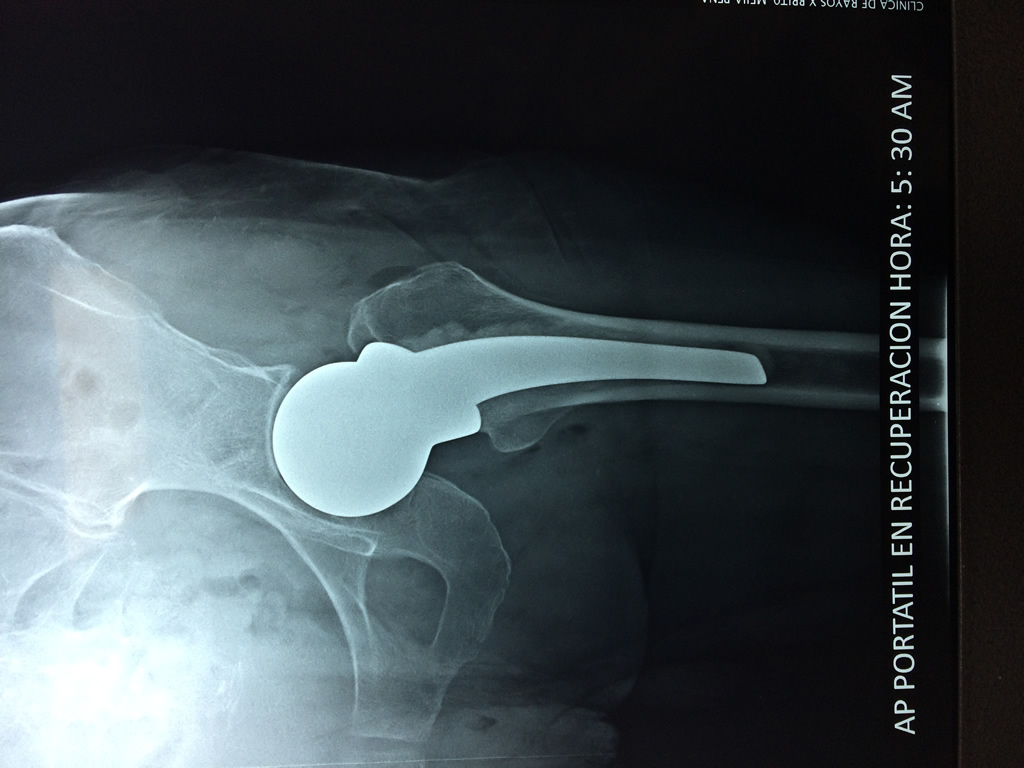

A menudo se recomienda la cirugía para reparar la fractura debido a dichos riesgos.

De esta forma nos ponemos a tus órdenes, somos conocedores de estos tipos de problemas, visitarnos será un gusto el poderte ayudar. cualquier inquietud puedes escribirnos al correo Esta dirección de correo electrónico está siendo protegida contra los robots de spam. Necesita tener JavaScript habilitado para poder verlo.